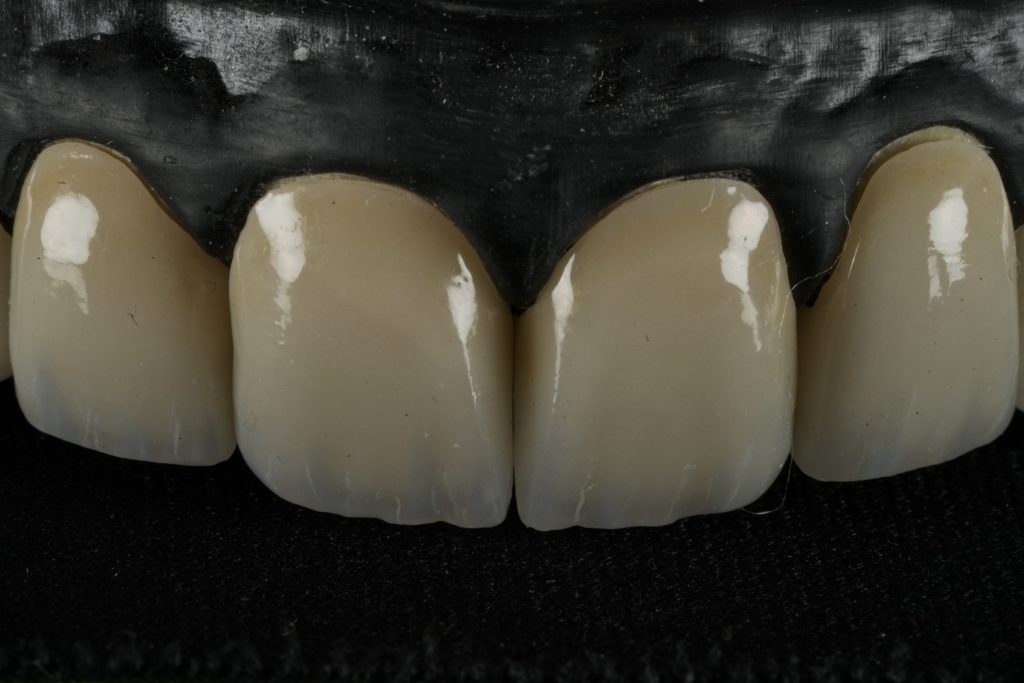

IPS E-max Press veneers were pressed and characterized using micro-layered incisal ceramics for vitality and translucency. Surface texture and internal effects were customized to simulate natural perikymata and halo zones (Fig 3).